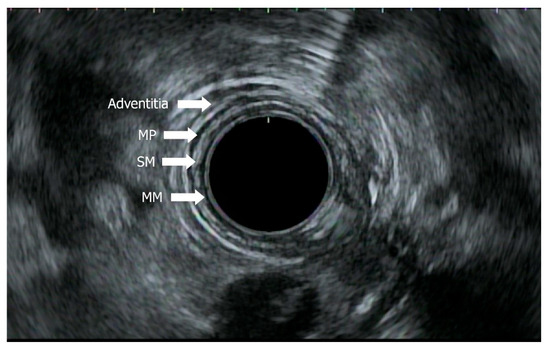

- Radlinski, M.; Shami, V.M. Role of endoscopic ultrasound in esophageal cancer. World J. Gastrointest. Endosc. 2022, 14, 205–214. [Google Scholar] [CrossRef]

- Thakkar, S.; Kaul, V. Endoscopic ultrasound staging of esophageal cancer. Gastroenterol. Hepatol. 2020, 16, 14–20. Available online: https://pubmed.ncbi.nlm.nih.gov/33867884/ (accessed on 29 May 2025).